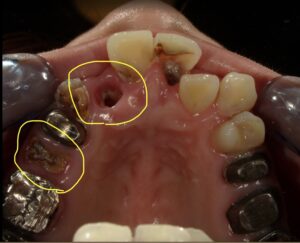

【歯科医師が解説】C4とは?歯のSOSサインを見逃さないで!

【歯科医師が解説】C4の歯で矯正はムリ?手遅れになる前に知るべき治療の順番と「最善の選択」